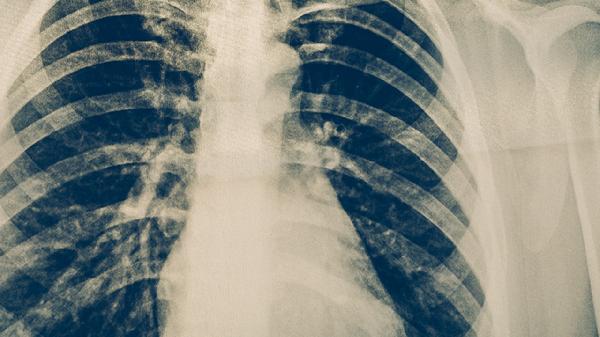

晨跑时的深呼吸能帮助扩张肺组织,促进肺部炎症吸收和病灶纤维化。适度有氧运动可提升血液循环效率,增强肺泡换气功能,改善慢性缺氧状态。阳光照射有助于维生素D合成,对结核杆菌抑制有辅助作用。运动后产生的内啡肽能缓解抗结核药物引发的消化道不适症状。规律的晨间运动可帮助建立良好生物节律,改善抗结核治疗期间的睡眠障碍。

重症活动性肺结核患者和存在咯血风险者应禁止跑步,以防诱发大咯血或病灶播散。伴有显著低氧血症的患者运动时可能出现头晕、心悸等缺氧加重表现。合并骨关节结核者跑步可能加重病灶部位机械损伤。糖尿病患者晨跑需警惕空腹运动引发低血糖反应。痰菌阳性患者在户外运动需做好防护避免传播风险。